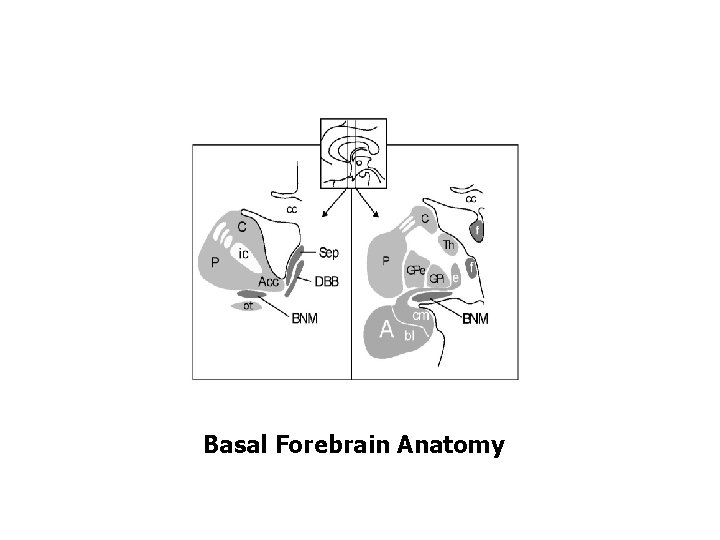

Basal Forebrain Anatomy